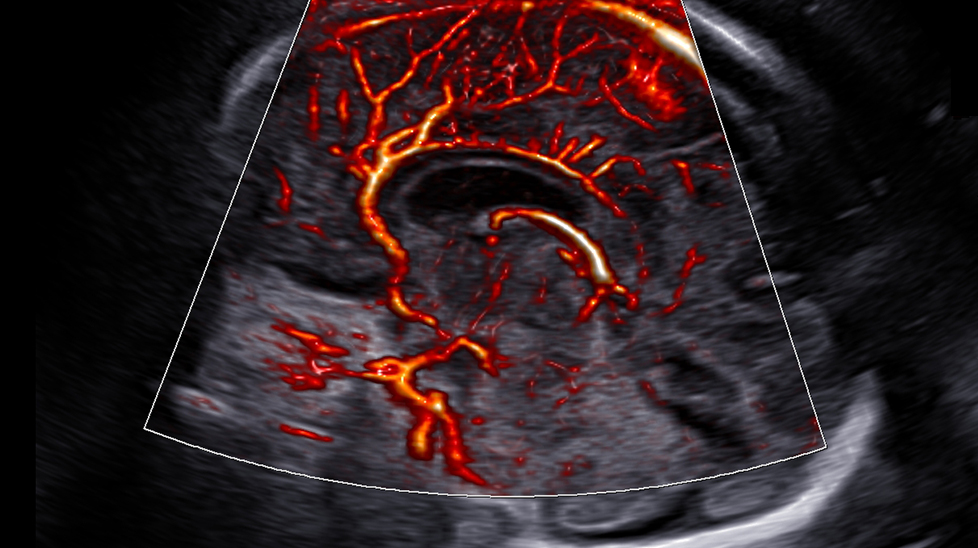

CrystalVue Flow™ ¹ is a volume rendering technology that provides additional information of blood flow morphology based on the CrystalVue™ features that visualizes the internal structures by projecting the 3D data, providing better understanding in the anatomic structures and surrounding vascular vessels.

The color imaging performance has been improved to clearly visualize the hemodynamics of the blood flow. A greater sensitivity resulting from new color signal processing and a realistic 3D visualization of blood flow help understand the microcirculatory blood flows, accurate detection of peripheral blood vessels, and volumes of slow blood flows.

LumiFlow™ is a function that visualizes blood flow in three dimensional-like to help understand the structure of blood flow and small vessels intuitively.

MV-Flow™ visualizes microcirculatory and slow blood flow to display the intensity of blood flow in color. It is suitable for observation of microcirculatory blood flow and volume of slow blood flow.

The function uses directional power Doppler technology, enabling you to examine even the peripheral vessels. It displays information on the intensity and direction of blood flow.